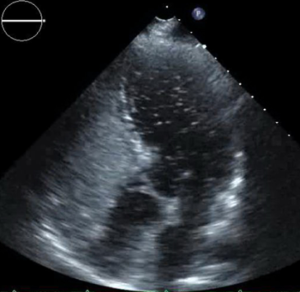

The PERT recommended further work up. Lower extremity venous ultrasound demonstrated evidence of a right popliteal deep venous thrombosis. Suspicion for intracardiac shunt as the source of the axillary arterial embolus prompted an evaluation with transthoracic echocardiogram with agitated saline “bubble study.” The echo revealed a mobile interatrial septum and early passage of “bubbles” from the right to the left atrium consistent with interatrial shunt likely patent foramen ovale (PFO) (Figure 6).